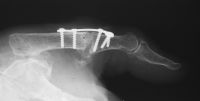

| Smaller plates and screws

from the Lorenz craniofacial fixation system were used for this MCP

fusion. |

| Low profile, but possibly

too small in terms of rigidity. Despite this concern, the patient did

well. |